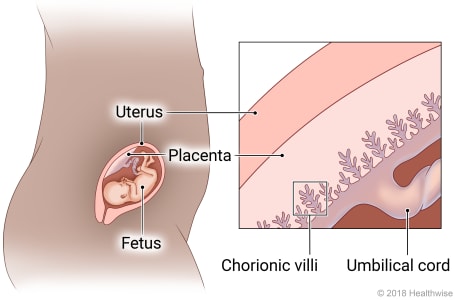

B. Chorionic Villi

Once implantation is complete, the trophoblastic layer of cells of the blastocyst begins to mature rapidly. As early as the 11th or 12th day, miniature villi that resemble probing fingers, termed chorionic villi, reach out from the single layer of cells into the uterine endometrium to begin the formation of the placenta. At term, almost 200 such villi will have formed (Knuppel, 2007).

All chorionic villi have a central core of connective tissue and fetal capillaries. A double layer of trophoblast cells surrounds these. The outer of the two covering layers is the syncytiotrophoblast or the syncytial layer (outer and inner). This layer of cells produces various placental hormones, such as hCG, somatomammotropin (human placental lactogen [hPL]), estrogen, and progesterone.

The middle layer, the cytotrophoblast or Langhans’ layer, is present as early as 12 days’ gestation. It appears to function early in pregnancy to protect the growing embryo and fetus from certain infectious organisms such as the spirochete of syphilis. This layer of cells disappears, however, between the 20th and 24th weeks. This is why syphilis is not considered to have a high potential for fetal damage early in pregnancy, only after the point at which cytotrophoblast cells are no longer present (Ainbinder, Ramin, & DeCherney, 2007). The layer appears to offer little protection against viral invasion at any point

The Placenta

The placenta (Latin for “pancake,” which is descriptive of its size and appearance at term) arises out of the continuing growth of trophoblast tissue. Its growth parallels that of the fetus, growing from a few identifiable cells at the beginning of pregnancy to an organ 15 to 20 cm in diameter and 2 to 3 cm in-depth, covering about half the surface area of the internal uterus at term.

Circulation

As early as the 12th day of pregnancy, maternal blood begins to collect in the intervillous spaces of the uterine endometrium surrounding the chorionic villi. By the third week, oxygen and other nutrients, such as glucose, amino acids, fatty acids, minerals, vitamins, and water, osmose from the maternal blood through the cell layers of the chorionic villi into the villi capillaries. From there, nutrients are transported to the developing embryo.

Placental osmosis is so effective that all except a few substances can cross from the mother into the fetus. Because almost all drugs can cross into the fetal circulation, a woman must take no nonessential drugs (including alcohol and nicotine) during pregnancy (Rogers-Adkinson & Stuart, 2007).

For practical purposes, because the process of osmosis is so effective, there is no direct exchange of blood between the embryo and the mother during pregnancy. Because the outer chorionic villi layer is only one cell thick after the third trimester minute breaks do occur and allow occasional fetal cells to cross into the maternal bloodstream, as well as fetal enzymes such as alpha-fetoprotein (AFP) from the fetal liver.

About 100 maternal uterine arteries supply the mature placenta. To provide enough blood for exchange, the rate of uteroplacental blood flow in pregnancy increases from about 50 mL/min at 10 weeks to 500 to 600 mL/min at term. The woman’s heart rate, total cardiac output, and blood volume increase to supply blood to the placenta

Uterine perfusion, and thus placental circulation, is most efficient when the woman lies on her left side. This position lifts the uterus away from the inferior vena cava, preventing blood from being trapped in the woman’s lower extremities. If the woman lies on her back and the weight of the uterus compresses the vena cava, placental circulation can be so sharply reduced that supine hypotension (very low maternal blood pressure and poor uterine circulation) occurs (Knuppel, 2007).

At term, the placental circulatory network has grown so extensively that a placenta weighs 400 to 600 g (1 lb), one-sixth the weight of the baby. If a placenta is smaller than this, it suggests that circulation to the fetus may have been inadequate. A placenta larger than this may also indicate that circulation to the fetus was threatened because it suggests that the placenta was forced to spread out unusually to maintain a sufficient blood supply. The fetus of a woman with diabetes may also develop a larger-than-usual placenta from excess fluid collected between cells.